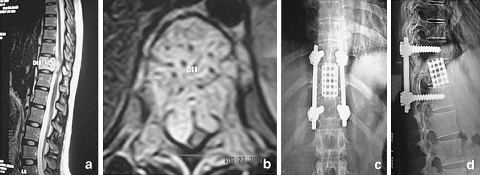

The X-ray showed an expansile lesion of D11 corpus extending to the pedicles with canal compromise without collapse. Keeping her pregnancy in mind an MRI was done, which showed features suggestive of a hemangioma involving the whole of the vertebral body with severe compression of the cord by a soft tissue mass and hemorrhage (Fig. 1a, b).

Fig. 1.

a, b Preoperative MRI scan: Showing expansion of the body, pedicles and transverse process of 11th thoracic vertebrae with an anterolateral epidural soft tissue component causing gross compression of the spinal cord. c, d Two years postoperative radiographs: pedicle screw instrumentation and reconstructive cage in situ, with no evidence of tumour recurrence

Nine months later the patient developed pain in the middle of the back. Clinical examination revealed intact neurology, but a repeat MRI showed expansion of the lesion. An embolization followed by an anterior corpectomy and fusion with a titanium cage was performed (Fig. 1c, d). At 28 months follow up the patient is asymptomatic with no residual neurological deficits.